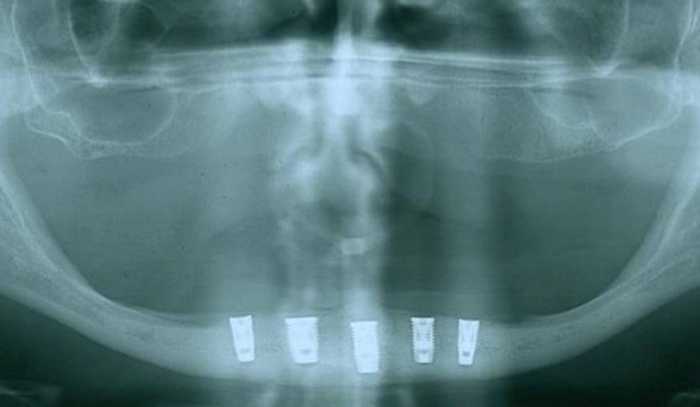

Raio X dos implantes Cone Morse

Raio X final com prótese fixa em resina instalada, sobre implantes Cone Morse